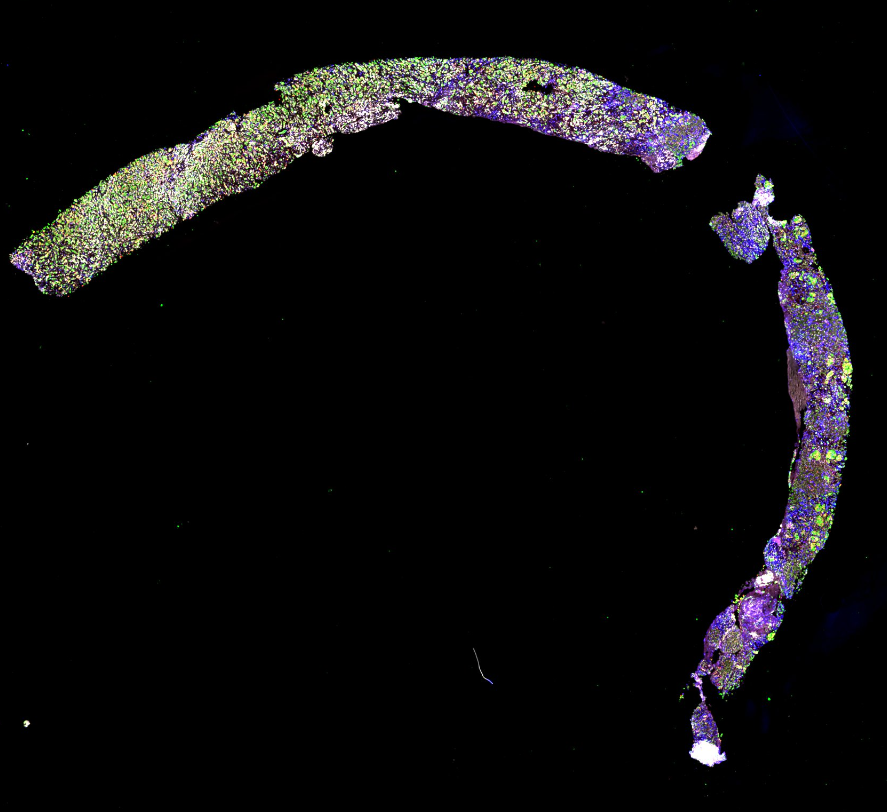

The Omic and Multidimensional Spatial Atlas

Click to enlarge.

The Omic and Multidimensional Spatial (OMS) Atlas Center based at the Oregon Health Sciences University (OHSU) and led by Joe Gray was a component of the National Cancer Institute Human Tumor Atlas Network (HTAN), a multi-center program within the National Cancer Institute that emerged from the Beau Biden Cancer Moonshot Initiative.

The OMS was focused on elucidating mechanisms of therapy resistance in three clinical scenarios in which disease recurrence is a major concern: (a) hormone-receptor positive breast cancer (HRBC) undergoing treatment with a CDK4/6 inhibitor in combination with endocrine therapy, (b) triple negative breast cancer (TNBC) undergoing treatment with a PARP inhibitor and an immunomodulatory agent (c) castration resistance prostate cancer (CRPC) undergoing treatment with enzalutamide. Diverse imaging and omic methods were applied to this analysis including several complementary ways to create spatial maps of cell types and states. These include multiplex immuno-histochemistry, CyCIF, Focused Ion Beam Scanning Electron Microscope (FIB-SEM).